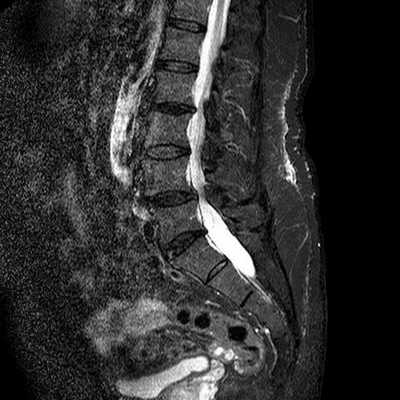

Стеноз позвоночного канала поясничного отдела на снимке МРТ

Для эффективного лечения болевого синдрома в области нижних отделов спины необходимо установить природу данного явления и уточнить локализацию патологического очага. Чаще в подобной ситуации лечащий врач рекомендует сделать МРТ пояснично-крестцового отдела, что показывает состояние морфологических элементов позвоночника и окружающих структур.

На снимках, полученных в результате магнитно-резонансной томографии, видны травматические повреждения спинного мозга при нарушении целостности тел позвонков, хрящей. Определяются разрывы и растяжения мышечной ткани, связочного аппарата. При компрессионных травмах МРТ визуализирует состояние церебральных структур, выявляет участки сдавливания нервных корешков.

Сканирование покажет локализацию и размеры новообразования, его взаимодействие с окружающими тканями. При наличии воспалительных и деструктивно-дистрофических процессов, которые послужили причиной болевого синдрома, МРТ помогает определить степень поражения тканей и точное расположение очага.